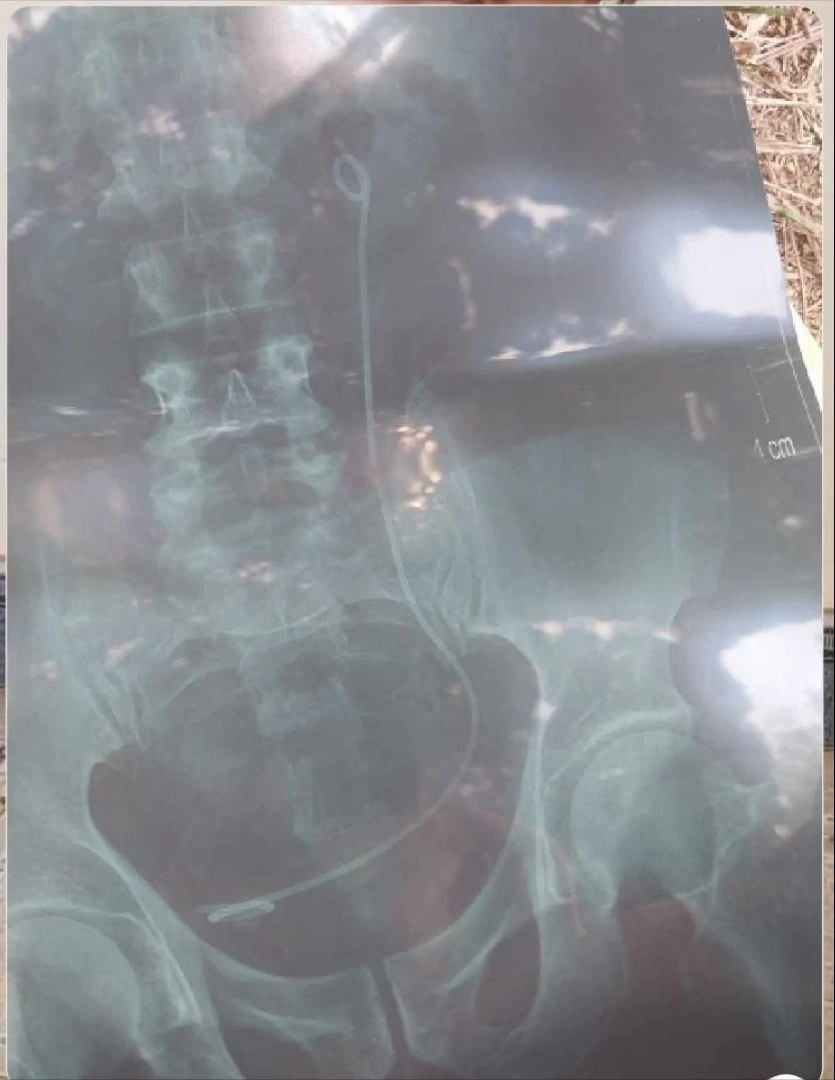

Trả nhầm X-quang của một bệnh nhân khác nên thủ thuật nội soi nhầm người

Tuy nhiên khi nhận lại kết quả chụp X-quang cho thấy trong bụng ông Hải có một đoạn dây nhựa dẫn nước tiểu dài.

Ông Hải được thực hiện thủ thuật nội soi trong ngày nhưng không tìm được đoạn dây như phim X-quang thể hiện, vì bộ phận chụp X-quang trả nhầm phim của một bệnh nhân khác đã mổ thận cách đây khoảng 40 ngày cho ông Hải.